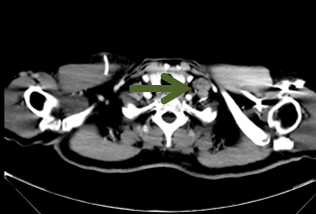

(2015/11/07我院胸腹盆CT):结肠癌术后 右卵巢转移;左锁上、下腔静脉旁、腹主动脉旁、左髂总血管旁淋巴结转移。

基线CT:

治疗前CT2015-10-21